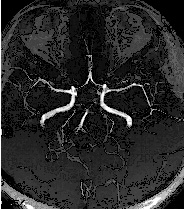

圖二

圖一、圖二由影像醫學科賴彥君醫師提供圖片及解說

這是另外一位受檢者,利用磁振血管造影顯示出大腦內部血管的狀況,主要的大腦血管均暢通,無明顯狹窄的情形。 此外,除了大腦內部的血管可探查清楚之外,雙側的頸動脈血管及更深部的椎動脈亦可在同一次檢查當中一目瞭然 (如上圖所示)